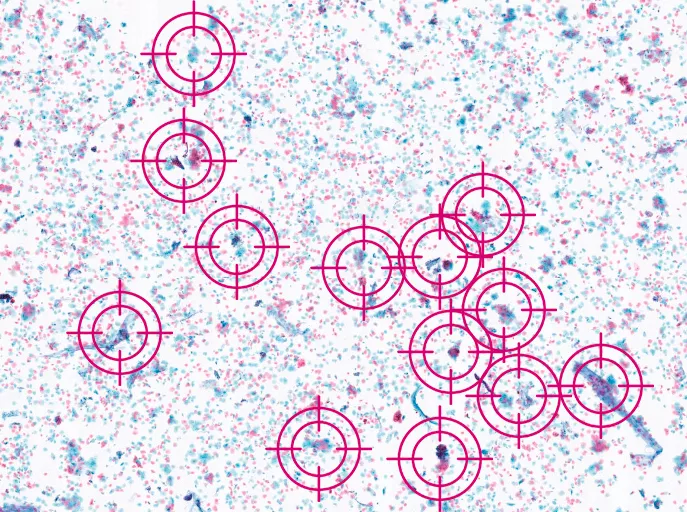

Your digital assistant targets cells that need expert attention.

Genius Cervical AI narrows your screening from tens of thousands of objects down to a curated gallery of images for targeted and efficient review.

Genius Cervical AI objectively analyzes every cell on a digital image and intelligently identifies those clinically relevant.

A single gallery representing the entire case is organized and presented, enabling reviewers to make an interpretation using only the AI-generated gallery of images.

The system can rapidly analyze all cells on a ThinPrep® Pap test digital image, narrowing tens of thousands of cells down to an AI-generated gallery of the most diagnostically relevant images. This will help provide healthcare providers with the critical information they need to guide earlier detection and better treatment decisions for the patients they serve.